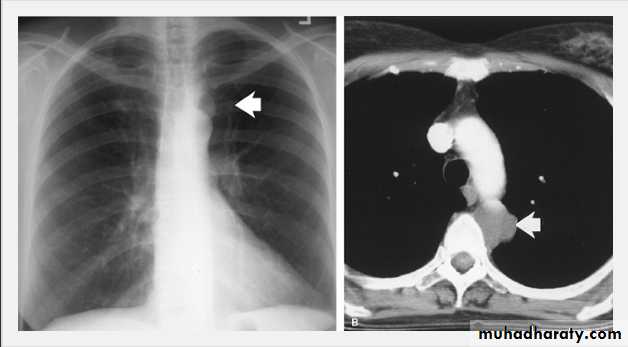

On a posteroanterior chest x-ray (A), the left hemithorax is very dark or lucent because the left lung has collapsed completely (white arrows).The tension pneumothorax can be identified because the mediastinal contents, including the heart, are shifted toward the right, and the left hemidiaphragm is flattened and depressed. A computed tomography scan done on a different patient with a tension pneumothorax (B) shows a completely collapsed right lung (arrows) and shift of the mediastinal contents to the left.

Tension Pneumothorax. Portable chest film in a 43-year-old woman with ARDS shows a large right pneumothorax with mediastinal shift and ipsilateral diaphragmatic depression, suggesting tension.

Air was evacuated under pressure during emergent placement of a right chest tube.